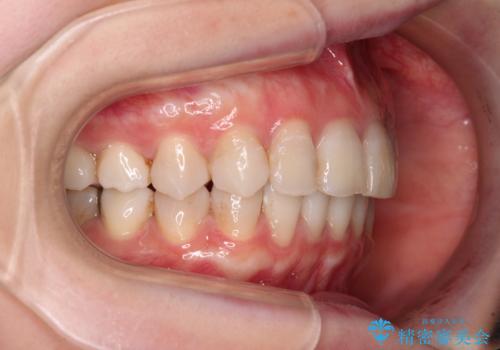

前歯の突出感とデコボコをインビザライン矯正で改善

- 上下前歯の突出感とデコボコを気にして来院された患者様です。

インビザラインによる上下歯列の側方拡大と後方移動、IPR(歯と歯の間を削る)にるスペースの獲得により歯列を整えることとしました。

骨格的な左右差があったため、上下の正中を合わせることができませんでした。

骨格の差は改善できないため、奥歯の咬み合わせに物足りなさを感じましたが、奥歯の咬み合わせによる不自由はなく、口元の突出感も改善することができました。